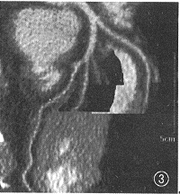

图3 中心线重组不会偏离血管中心,始终反映最大径,而且能显示整个血管树。此例为正常的左冠状动脉

图4 与图3同一数据,曲面重组容易偏离血管中心线,造成酷似狭窄的伪像(箭头)

MAR和CPR处理的正常冠状动脉EBCT造影图像分别示于图3、4,1例病变冠状动脉的造影、MAR、CPR图像分别示于图5~7。从中可以看出MAR具有以下特点(图3~12)。

1.MAR能保证曲截面准确贯穿血管轴线,从而保证反映血管最大径。而CPR靠徒手画曲线,不易掌握,也不能保证客观性,一旦画偏,则造成狭窄伪像。

2.MAR能够1次显示整个血管树,突破了CPR 1次只能显示1支血管的局限。